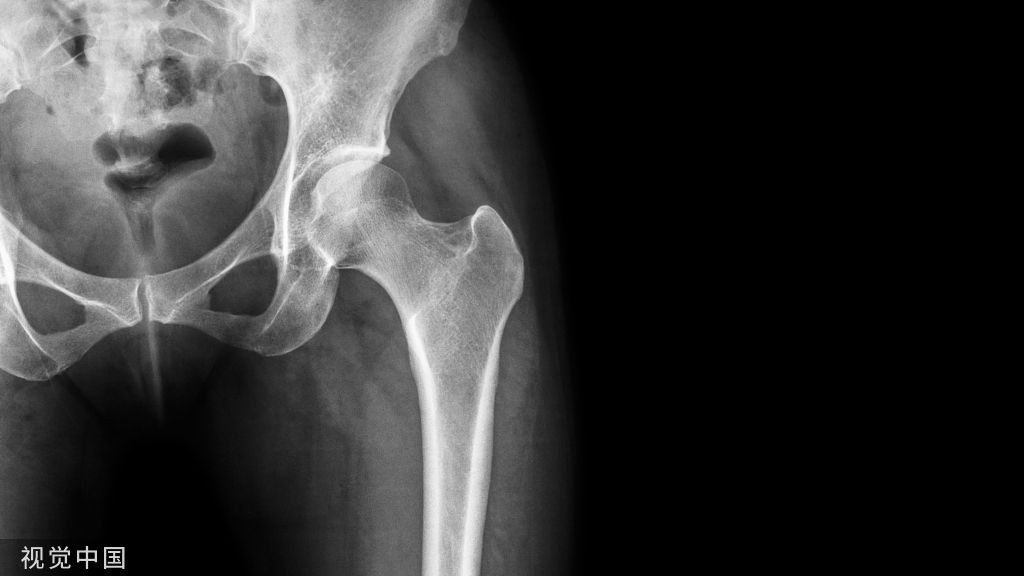

(一)下颌骨的组成

下颌骨由下颌体和下颌支两部分组成,呈马蹄形。下颌体分为内面、外面、牙槽突和下颌体下缘。

下颌支由喙突、髁突、内、外面四部分组成。下颌骨牙槽突的内侧骨板和外侧骨板都由骨密质构成,骨松质被内外侧骨板包绕其中(图1~3)。

图1 全景片全景片显示下颌骨的组成